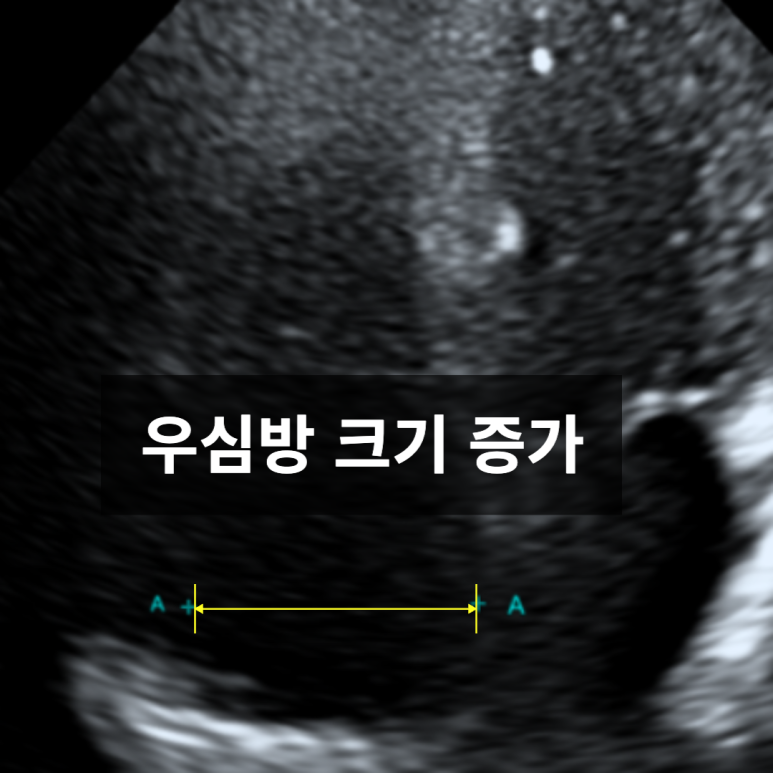

심방중격결손(ASD)은 성인에서도 발견될 수 있는 선천성 심장기형입니다. 본 사례는 초음파에서 좌심방과 우심방 사이의 결손으로 좌심방→우심방으로의 비정상적인 혈류 이동우심방비대가 확인되었습니다.

심방중격결손으로 인한 비정상적인 혈류이동으로 인해 우심방에 부담이 커지면서 우심방 비대가 초음파로 확인됨. 추가 검사 및 시술이 필요할 가능성이 있어 상급병원으로 전원.

• 초음파 검사: 심방중격결손 초음파 검사: 심방중격결손

• 좌심방과 우심방사이 비정상적인 혈류 이동 좌심방과 우심방사이 비정상적인 혈류 이동

• 우심방 비대 우심방 비대